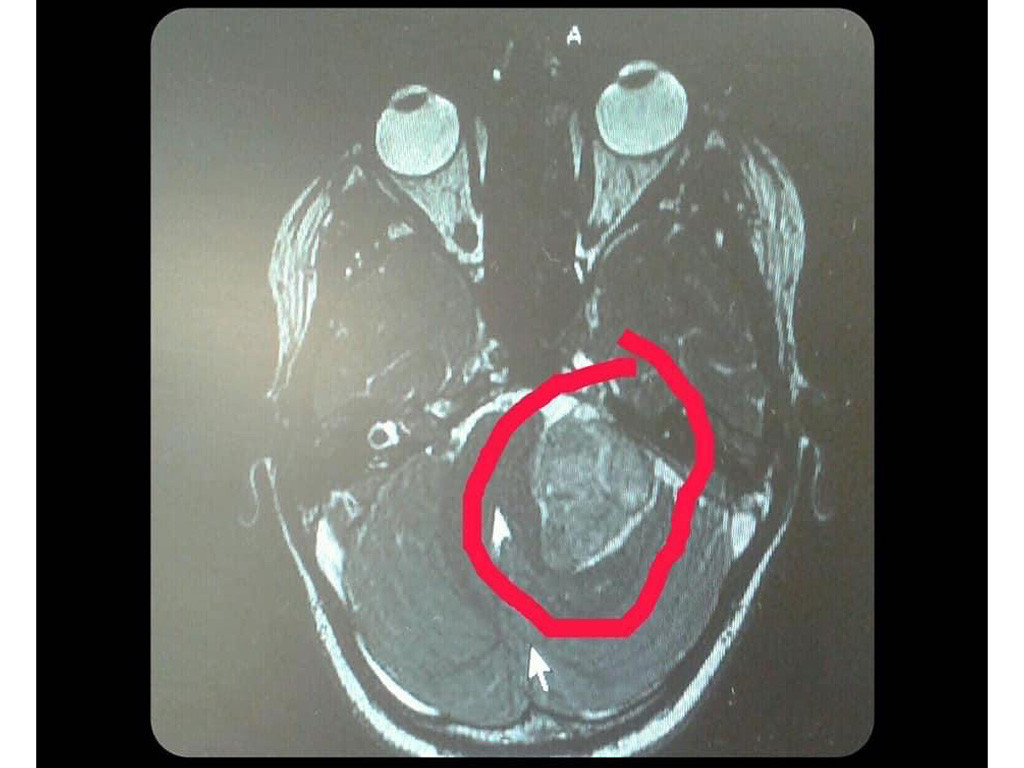

I then got sent for an MRI scan, they found a benign tumour. After seeing ENT doctors, tests & stuff I got the diagnosis of NF2. I then had an appointment with genetic testing to establish the diagnosis again.

In 2017, I had my first surgery to have the first benign tumour (acoustic neuroma) removed, it was the size of a strawberry. After surgery, I lost complete hearing in my left ear. I now rely on wearing a hearing aid in my right ear.